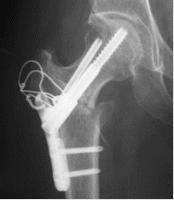

大腿骨頭壊死に対する骨温存手術として、大腿骨骨切術、減圧骨移植術を、年齢や骨壊死範囲、社会的状況を考慮して行っております。いずれの手術でも、術後6週間後から部分荷重を開始し、退院は2ヶ月程度で可能となります。

48歳、大腿骨頭前方回転骨切術後半年

術後3年